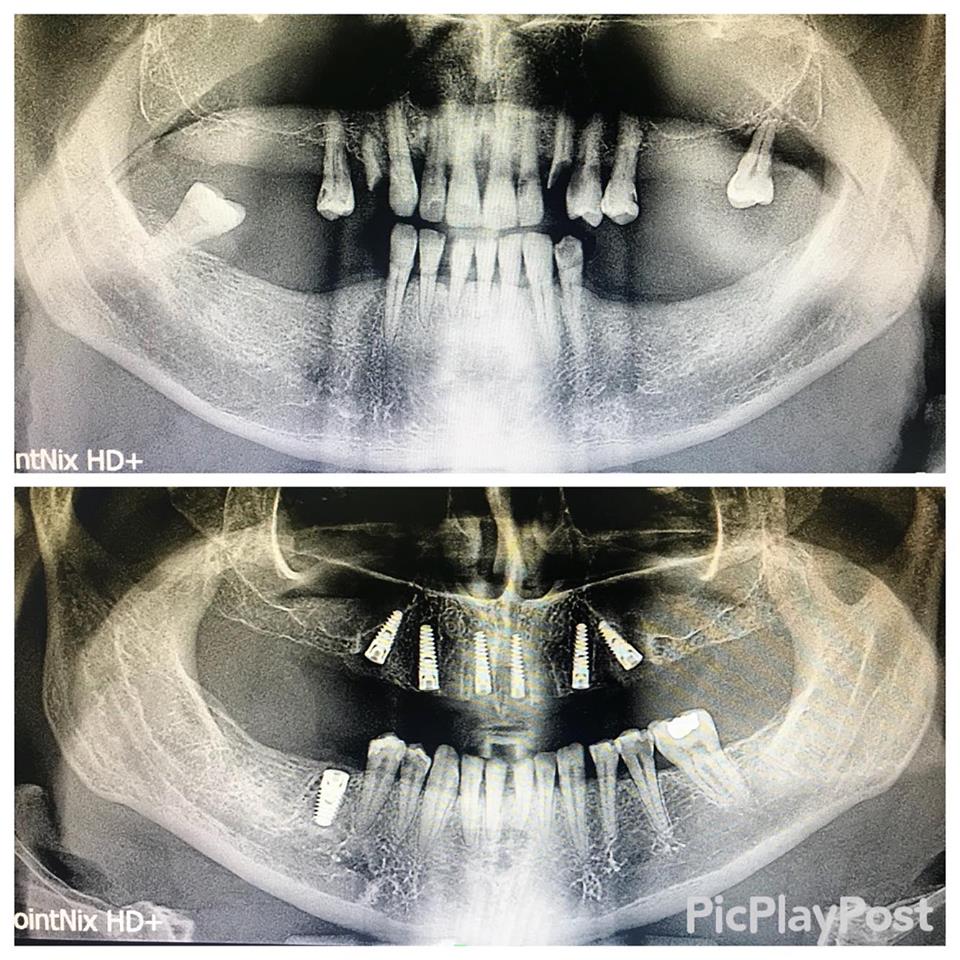

İMPLANT TEDAVİSİ

implant tedavisi